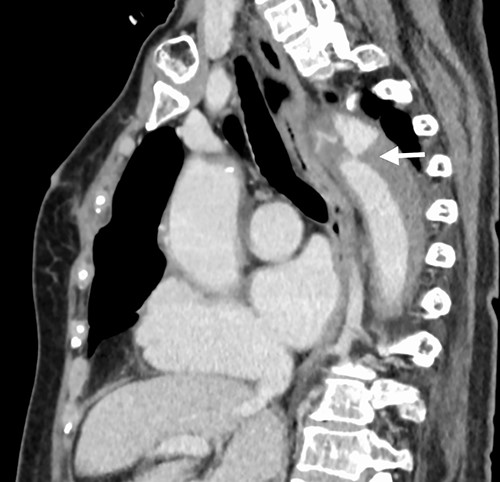

A 76-year-old woman with a giant retroperitoneal tumor was scheduled for surgical resection (Fig. 1). However, preoperative examination revealed severe aortic valve stenosis (AS); therefore, the patient first underwent minimally invasive aortic valve replacement (MICS-AVR) for severe AS. In this operation, we approached the surgical site through the right third intercostal space, and cardiopulmonary bypass was established with right femoral arterial and venous cannulation. PERCEVAL (Livanova, London, UK), a sutureless valve, was used as the artificial valve. Five days post-operatively, she complained of back pain, and a computed tomography (CT) scan revealed bleeding in the tumor and tumor growth. There were no findings of aortic dissection. A peripheral branch of the left third lumbar artery seemed to be the bleeding site; thus, lumbar artery transcatheter artery embolism (TAE) was performed. Although the bleeding stopped, early surgery was considered to be appropriate for the tumor. Therefore, retroperitoneal tumor resection and left nephrectomy were performed on the 12th post-operative day. Four days after tumor resection, the patient suddenly experienced persistent back pain again. CT revealed a Type B AAD. The aorta was dissected from the distal part of the left subclavian artery (LSA) to the level of the right renal artery, and an ulcer-like projection (ULP) was observed at the distal arch (Fig. 2). Although conservative treatment was started immediately, her back pain persisted and follow-up CT revealed slight growth of the ULP. Thus, we decided to perform thoracic endovascular aortic repair (TEVAR) using Valiant (Medtronic, Minneapolis, USA). Before the TEVAR procedure, we performed extra-anatomical bypass from the left common carotid artery to the LSA using PROPATEN (Gore, USA). The Valiant was deployed from Zone2 to just above the celiac artery (Fig. 3). The post-operative course was uneventful, and the patient was discharged without any complications. One year after discharge, CT showed that the aorta was remodeled almost as before (Fig. 4).

Arrow shows false lumen. (a) One week after TEVAR. False lumen still remains. (b) One year after TEVAR. False lumen has almost disappeared.